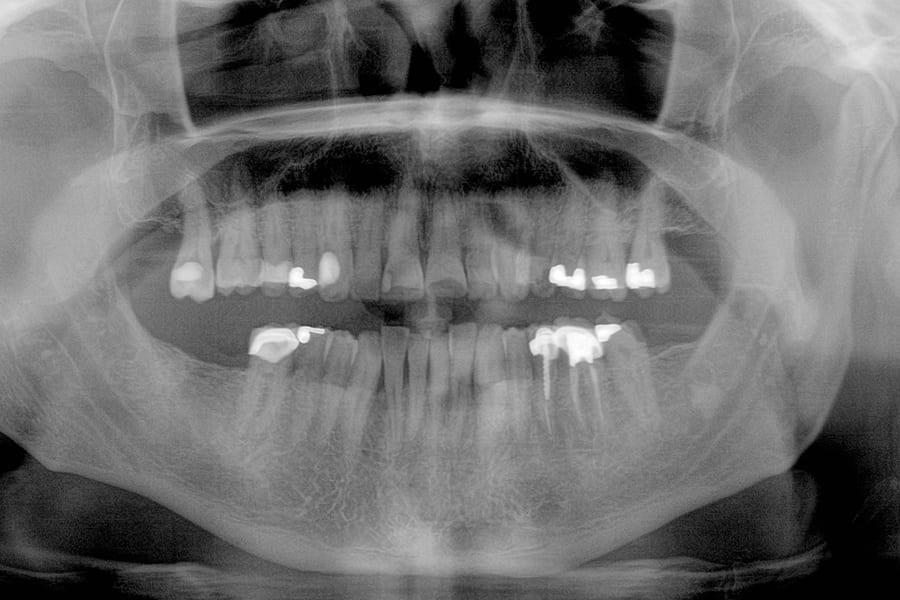

Клиническая потеря прикрепления 3–4 мм, локально до 5–6 мм. Фуркации II степени у зубов 3.6 и 4.6. Генерализованно 20 участков кровоточивости при зондировании. Классификация AAP: стадия III, градация B (Фото 4).

Фото 4. Панорамная рентгенограмма до лечения.